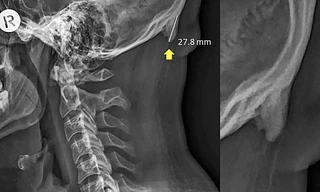

TPO - Đau vai gáy khá phổ biến nhưng dễ nhầm lẫn với các bệnh lý cần phân biệt: Lao cột sống, các bệnh lý tuyến giáp, u đỉnh phổi, u tại cột sống, u tủy sống…Để chẩn đoán bệnh lý đau cổ vai gáy, người bệnh nên đến cơ sở y tế để được khám chuyên khoa cẩn thận; các dấu hiệu lâm sàng sẽ được khai thác đầy đủ; các cận lâm sàng cần làm chính xác.

TPO - Đau vai gáy là triệu chứng thường gặp đặc biệt là ở dân văn phòng. Tuy nhiên không chỉ đơn giản như vậy. đây có thể lại là triệu chứng của nhiều bệnh lý nguy hiểm khác mà ít người biết.